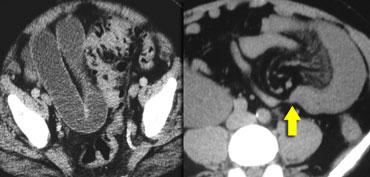

Ca lâm sàng bên trái cho thấy một bệnh nhân khác bị tắc ruột dạng quai kín.

Mặc dù các mạch máu ngấm thuốc tốt, nhưng dường như thành ruột không ngấm thuốc.

Các dấu hiệu thiếu máu cục bộ khác trong ca này bao gồm phù nề mạc treo và dày thành ruột.

Ruột bị nhồi máu được phát hiện trong quá trình phẫu thuật.

Nếu quai kín dài hơn và định hướng vuông góc với mặt phẳng cắt, chúng ta sẽ thấy một cụm quai ruột như trong ca lâm sàng bên trái.

Đôi khi điều này khó nhận biết chỉ trên các lát cắt ngang và các tái tạo mặt phẳng coronal hoặc sagittal có thể hữu ích.

Trong ca này, cũng có phù nề mạc treo và cổ